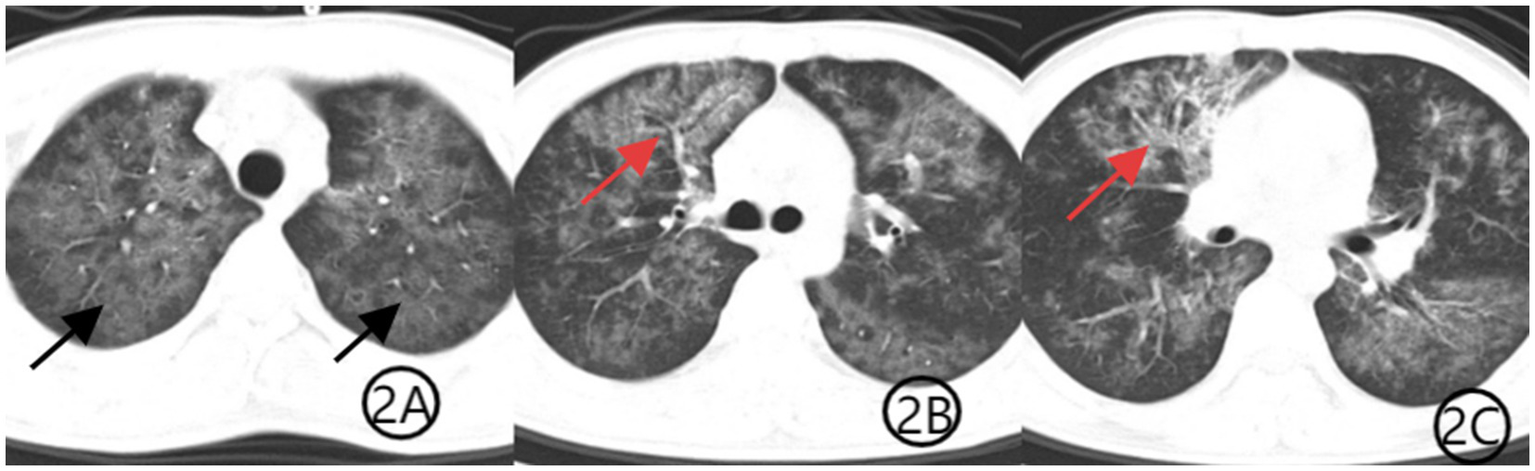

Figure 2

(A–C) Chest CT scan after 1 week of treatment. Axial CT images show improvement in bilateral diffuse ground-glass opacities (black arrows), indicating partial resolution of PJP. The patchy consolidation in the anterior segment of the right upper lobe is markedly reduced, with decreased visibility of the air bronchogram sign (red arrows), consistent with treatment response to TW infection.